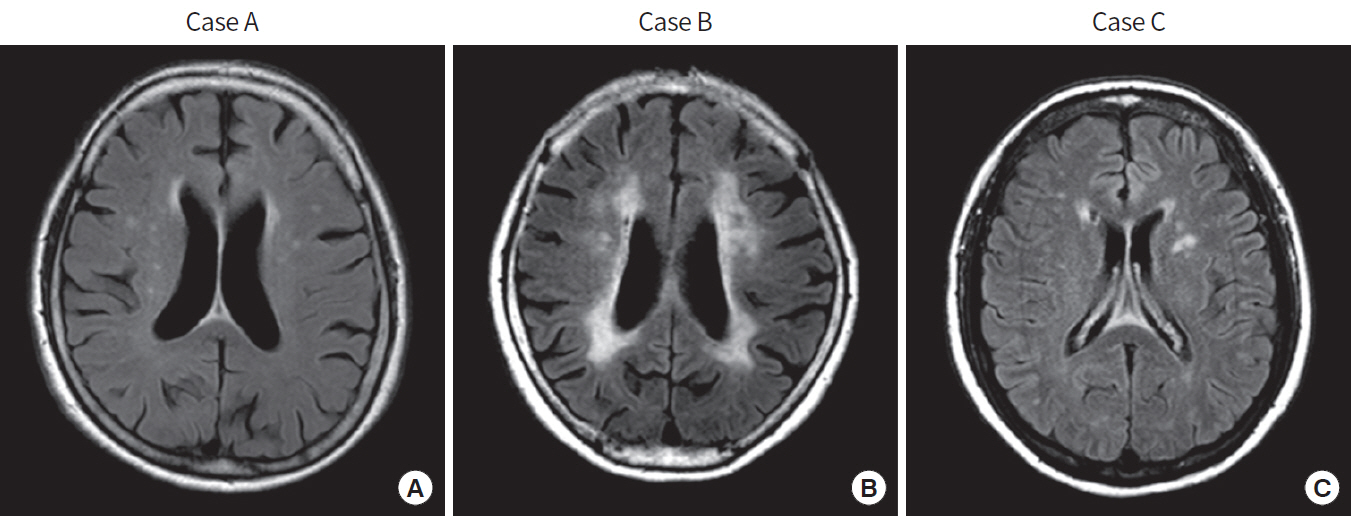

1. 신속한 평가 및 진단: 뇌경색 초기증상과 징후를 신속하게 인식하는 것은 적시에 개입하고 환자 결과를 개선하는 데 필수적입니다. 의료 전문가는 NIHSS(National Institutes of Health Stroke Scale)와 같은 도구를 사용하여 잠재적인 뇌경색 환자를 신속하게 평가하고 컴퓨터 단층 촬영(CT) 스캔 또는 자기 공명 영상(MRI)을 포함한 진단 테스트를 시작하여 진단을 확인하고 유형을 결정해야 합니다.